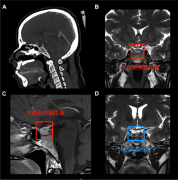

37岁的女士珍妮(化名),近几个月来,月经紊乱,并且经常感到腰背跳痛。然后到当地的Lariboisiere医院检查,术前磁共振成像(MRI)显示位于蝶鞍中央的9mm微腺瘤,被诊断为垂体瘤,月...

垂体瘤 是常见的颅内肿瘤。对于垂体瘤的治疗,药物治疗或经蝶窦手术通常是泌乳素瘤和其他腺瘤亚型的一线治疗方法。由经验丰富的外科医生进行蝶窦手术,治愈率为60-80%。视肿瘤的...

切除垂体肿瘤的手术通常由神经外科医生进行,这是一名专门治疗包括大脑和脊柱在内的中枢神经系统疾病的外科医生。切除垂体肿瘤较常见的方法是经蝶入路,外科医生通过鼻子插入...